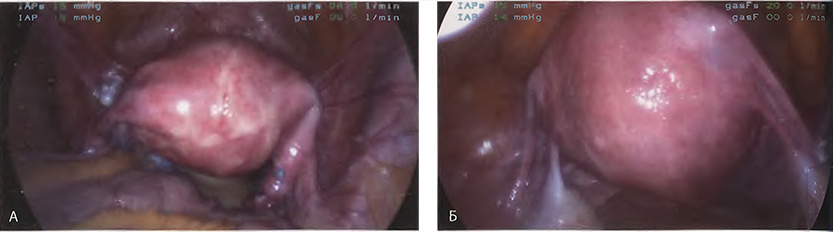

Если оставить в стороне эти достоинства и недостатки, то техника лапароскопической гистерэктомии фактически идентична технике лапаротомической гистерэктомии. В самом начале операции, если она выполняется лапароскопическим методом, необходимо осмотреть всё операционное поле, воспользовавшись для этого панорамным обзором (рис. 12-33—12-37). Операцию начинают с коагуляции и пересечения круглых связок, чем обеспечивается доступ к широкой связке (рис. 12-38—12-40). Брюшину, переходящую с купола мочевого пузыря на переднюю поверхность матки, вскрывают. Пузырь отсепаровывают от матки острым путём (рис. 12-41). После этого вскрывают задний листок широкой связки, а затем принимают решение, оставлять или удалять яичники. Если принято решение оставить яичники, то коагулируют и пересекают собственные связки яичников и маточные трубы (рис. 12-42). Если принято решение удалить яичники (то есть выполнить сальпингоофорэктомию), то с обеих сторон выполняют диссекцию мочеточников от воронко-тазовых связок, которые затем отсепаровывают, коагулируют и пересекают (рис. 12-43). Затем ткань широкой связки отделяют от маточных сосудов (отпрепаровывая их), изолировав, таким образом, мочеточники от маточных сосудов (рис. 12-44 А). Восходящие ветви маточных сосудов коагулируют справа и слева, а затем пересекают (рис. 12-44 Б, В).

Рис. 12-33. А. Лапароскопический вид матки на месте (in situ). Б. Увеличенное изображение матки и образований широких связок.